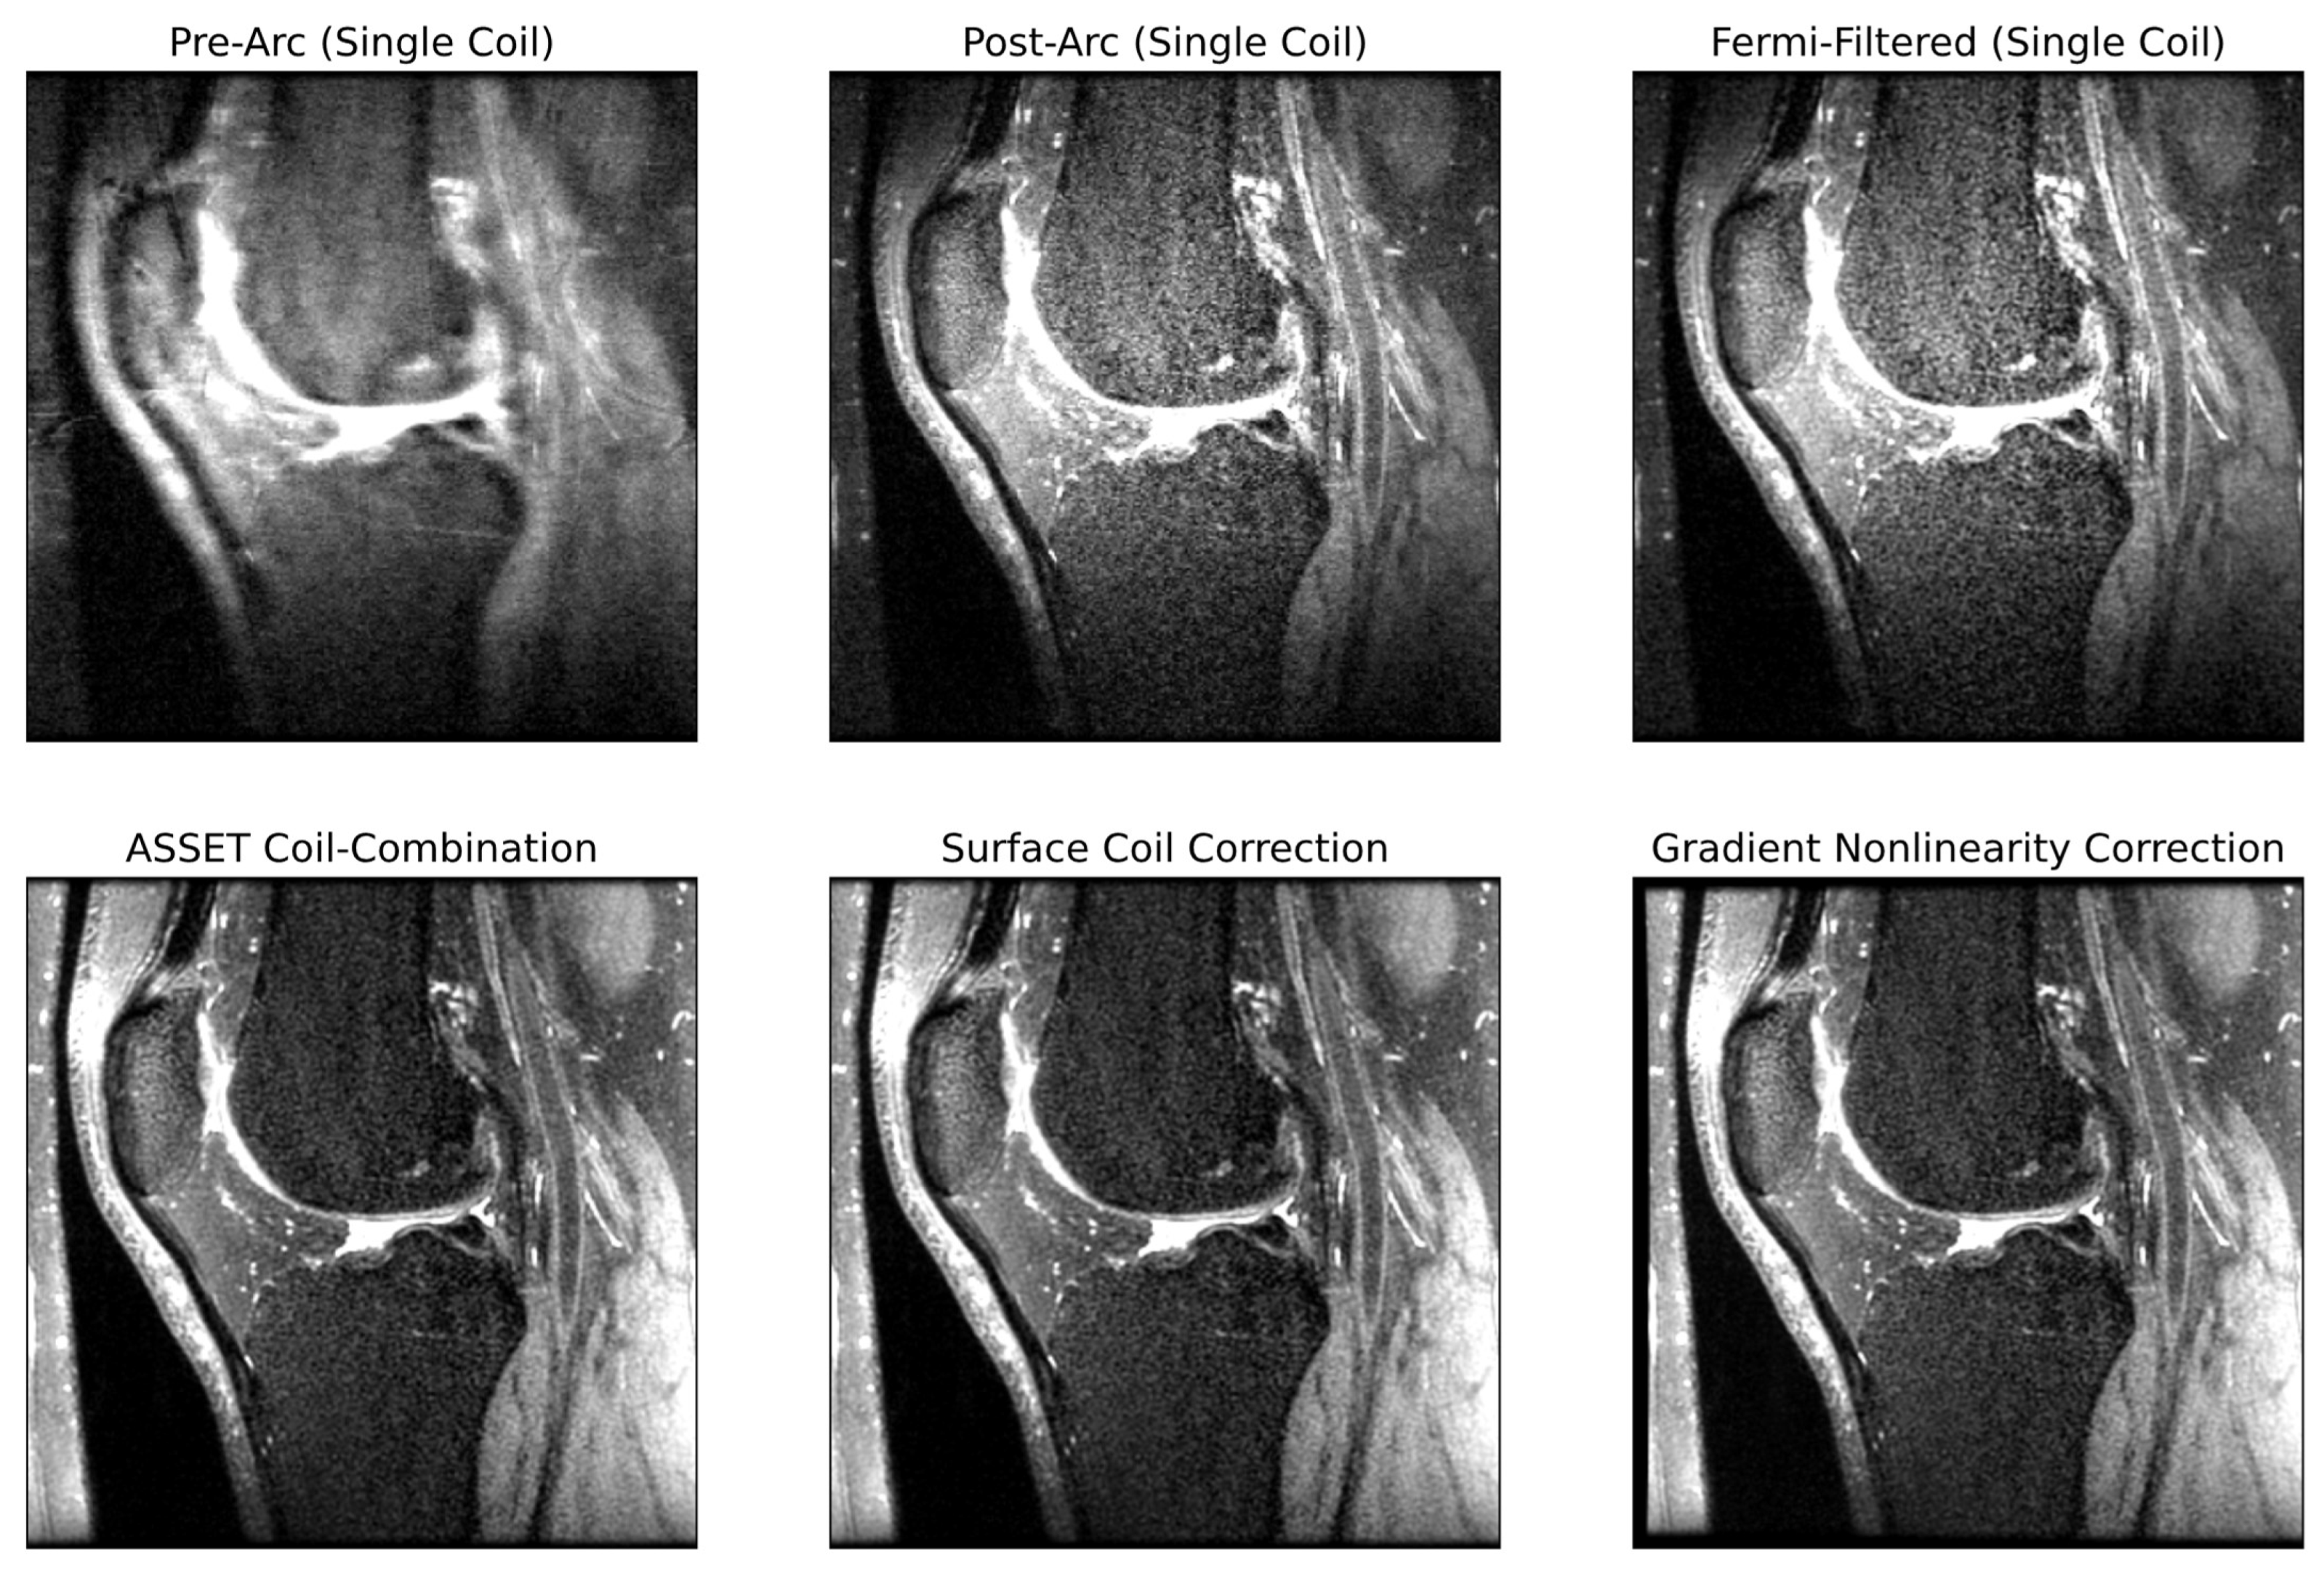

An in-house pipeline was developed replicating all post-processing steps done on an MR scanner to go from raw k-space data to DICOM images viewed by clinicians for diagnostic decisions. To the best of the authors’ knowledge, no centralized resource is available describing all these steps, which can make it difficult for those interested in reconstruction to familiarize themselves with the process before model development. The authors thus saw value in describing these steps, shown schematically in Figure 2, with examples of pipeline intermediates at several steps in Figure 3. Unless otherwise specified, all post-processing steps were implemented using functions in GE Orchestra 1.10.

Some sequences may leverage PI techniques (such as ARC or GeneRalized Autocalibrating Partial Parallel Acquisition (GRAPPA)) to acquire fewer lines within k-space, instead exploiting already acquired data across multiple coils to mitigate aliasing artifacts at the expense of SNR [17,45]. This was the case for our sequence; consequently, the first step in post-processing raw multicoil k-space data was applying ARC to impute unacquired k-space lines. Subsequently, Fermi filtration was applied: given MR images are often zero-padded in k-space, ringing artifacts can emerge from the sharp boundary in k-space between nonzero and zero points [46]. A Fermi filter smooths this boundary, reducing ringing artifacts at the expense of sharpness in the reconstructed image. A custom Fermi filtration function was used, using the Fermi filtration radius and width parameters extracted from raw sequence metadata. After Fermi filtration, k-space was zero-padded to the intended image dimensions (in our case, from 256 × 256 × 200 to 512 × 512 × 200), completing k-space post-processing. All k-space post-processing was on multicoil data.

Image Space Post-Processing

Post-processed k-space was 3D inverse Fourier transformed to image space for each of the 18 coils and coil-combined to yield a single-coil image. The most basic means of coil combination is root sum-of-squares, but GE provides another method based on Array coil Spatial Sensitivity Encoding (ASSET), which leverages sensitivity maps in a PI-inspired technique to do coil combination [47]. Magnitude images were then calculated, after which GE’s Phased array Uniformity Enhancement (PURE) was used to perform surface coil intensity correction [48,49]. This was followed by GRADWARP, which warps images to correct for inhomogeneities in gradient coils [50]. A final step in post-processing was correcting image orientation and scaling pixel values, yielding DICOM images used by clinicians for diagnostic purposes.

Figure 3. Intermediate outputs within the post-processing pipeline going from raw k-space to DICOM images. Each pane of the image reflects the output of the image after the step described by the pane title.